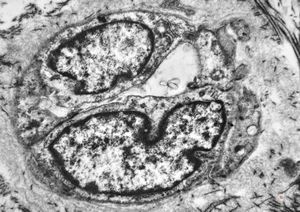

F,41y. | synovial metaplasia - capsule of implantate